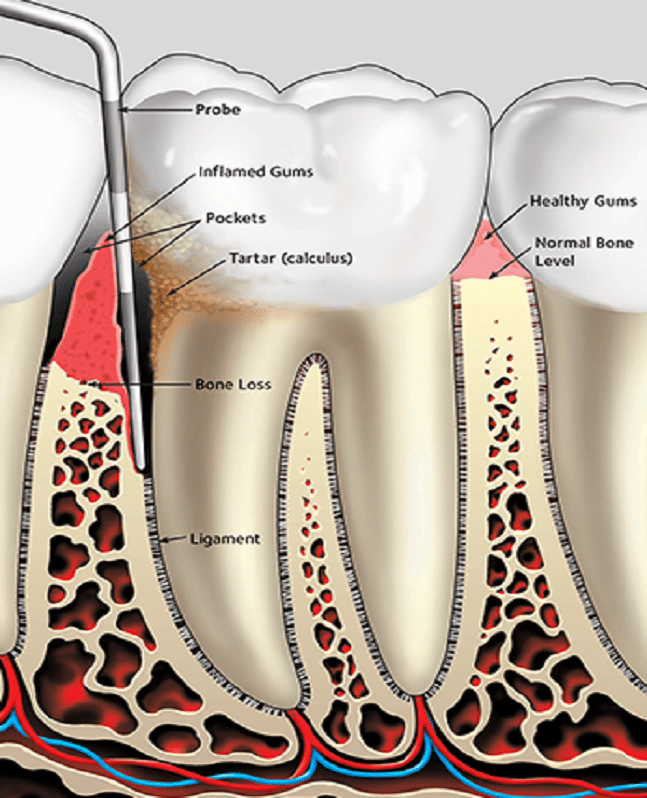

Παλαιότερες μελέτες παρατήρησης έχουν επιβεβαιώσει τη συσχέτιση μεταξύ ασθενών με ρευματοειδή αρθρίτιδα ΡΑ και υψηλότερων επιπέδων περιοδοντικής νόσου (νόσου των ούλων). Τα αντισώματα κατά των πρωτεϊνών κιτρουλλινικής προέλευσης (ACPA) βρίσκονται στο αίμα των περισσότερων ασθενών με ρευματοειδή αρθρίτιδα ΡΑ.

Η συσχέτισή τους είναι τόσο στενή ώστε τα αντισώματα κατά των πρωτεϊνών κιτρουλλινικής προέλευσης ACPA που ανιχνεύονται στο αίμα αποτελούν το καλύτερο εργαλείο έγκαιρης ανίχνευσης για μελλοντική παθολογία της ρευματοειδούς αρθρίτιδας ΡΑ, καθώς μπορούν να προηγηθούν της κλινικής διάγνωσης κατά αρκετά έτη. Η νόσος των ούλων είναι συγκεκριμένα πιο συχνή σε άτομα με ρευματοειδή αρθρίτιδα ΡΑ που έχουν επίσης αντισώματα κατά των πρωτεϊνών κιτρουλλινικής προέλευσης ACPAs στο αίμα τους.

Σε μια μελέτη με επικεφαλής το Πανεπιστήμιο του Στάνφορντ, οι ερευνητές θέλησαν να διερευνήσουν αν αυτές οι επικαλυπτόμενες παρατηρήσεις θα μπορούσαν να συνδεθούν καλύτερα. Οι ερευνητές ανέλυσαν βακτηριακό RNA σε δείγματα αίματος που συλλέχθηκαν από ομάδα 5 ασθενών με ρευματοειδή αρθρίτιδα ΡΑ με και χωρίς νόσο των ούλων σε εβδομαδιαίες χρονικές στιγμές επί ένα έτος. Εντόπισαν υπογραφές RNA μέσα σε ομάδες ενεργοποιημένων ανοσοκυττάρων που συσχετίζονταν τόσο με την παρουσία στοματικών βακτηρίων στο αίμα όσο και με τις εξάρσεις της αρθρίτιδας σε ασθενείς τόσο με ρευματοειδή αρθρίτιδα ΡΑ όσο και με περιοδοντική νόσο. Διαπιστώθηκε ότι τα βακτήρια ήταν κιτρουλλιωμένα (τροποποιημένα ενζυμικά) και αυτή η μεταβολή παρείχε τους στόχους για την επίθεση των αντισωμάτων κατά των κιτρουλλιωμένων πρωτεϊνών, καθώς και την αύξηση του αριθμού των αντισωμάτων που ανταποκρίνονταν.